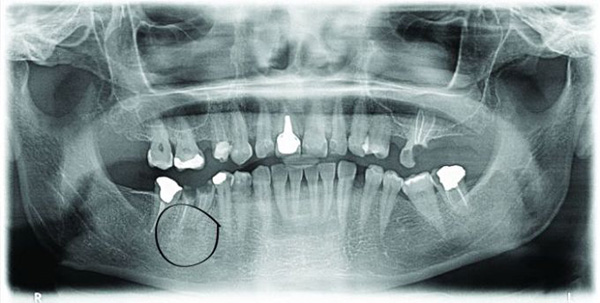

The last OPG image shows the implant (SP Straumann 4,1) 3 months after the extraction of the tooth and the placement of the implant. You can see that the implant has grown completely with the bone and that it is ready for the placement of the rest of the tooth. photo No. 3.

In my experience, when the initial situation is not ideal, that is, when extraction wounds, infections or lack of bone tissue are present, only Straumann dental implants can guarantee a successful dental implantology treatment.